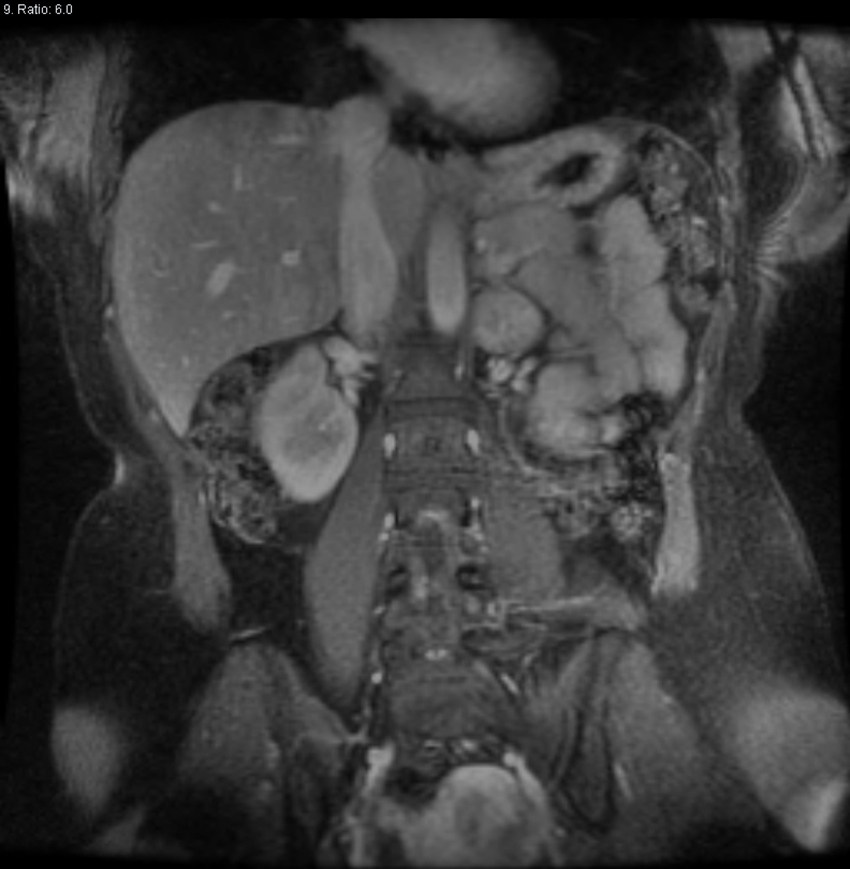

What is a Pheochromocytoma?

Pheochromocytoma is a catecholamine producing neuroendocrine tumor found in the adrenal medulla

1) Patients will have high sympathetic activity due to increased release of norepinephrine and epinephrine

→ patients will be sweating, hypertension, and tachycardic due to alpha and beta activation

→ patients will be dehydrated due to intravascular constriction

2) Important testing includes plasma or urine fractionated metanephrine + normetanephrines levels

→ all patients need genetic testing to rule out genetic syndromes

3) Treated with surgery but you need to perform an alpha and beta blockade